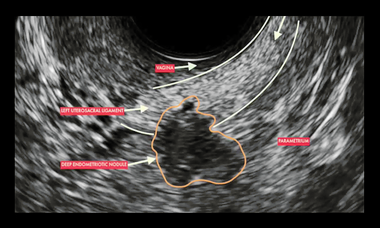

Ultrasound for diagnosis and pre-surgical staging of deep endometriosis (DIE): Supplement your learning

Supplement your learning for the ISUOG Pre-Congress Course "Ultrasound for diagnosis and pre-surgical staging of deep endometriosis (DIE)."